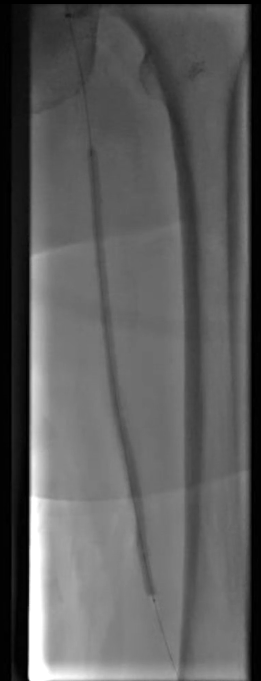

沿已建立轨道,选用4.0×150mm PTA球囊对股浅动脉闭塞病变段进行预扩张,为后续药物球囊治疗创造条件。